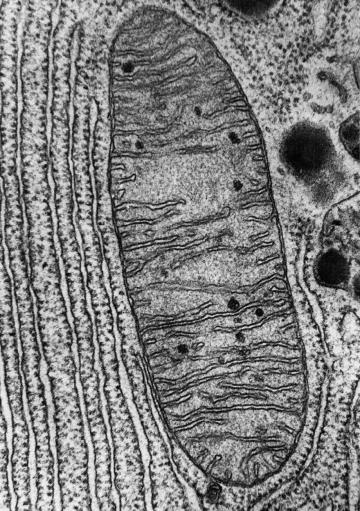

Since well before he became interested in hypoxia, Mootha has been fascinated with mitochondria: tiny structures within cells that act like power plants, using oxygen to make the energy our bodies need to function. When mitochondria don’t function well, cells can’t use oxygen efficiently, starving organs like the brain, muscles, and heart of a key fuel they need to operate. There are hundreds of rare genetic diseases that cause mitochondrial dysfunction. Those diseases can lead to neurological issues, organ failure, and death; no effective treatments exist to reverse their progression.

Photo: courtesy of Massachusetts General Hospital Department of Molecular Biology